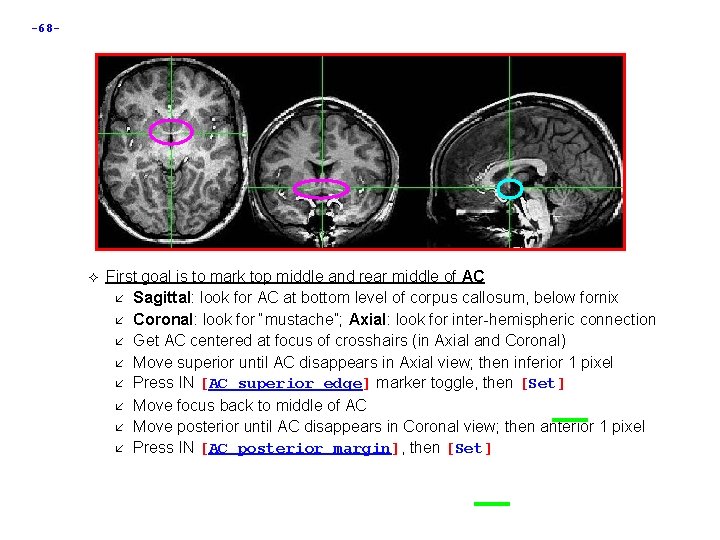

-68 - First goal is to mark top middle and rear middle of AC Sagittal: look for AC at bottom level of corpus callosum, below fornix Coronal: look for “mustache”; Axial: look for inter-hemispheric connection Get AC centered at focus of crosshairs (in Axial and Coronal) Move superior until AC disappears in Axial view; then inferior 1 pixel Press IN [AC superior edge] marker toggle, then [Set] Move focus back to middle of AC Move posterior until AC disappears in Coronal view; then anterior 1 pixel Press IN [AC posterior margin], then [Set]